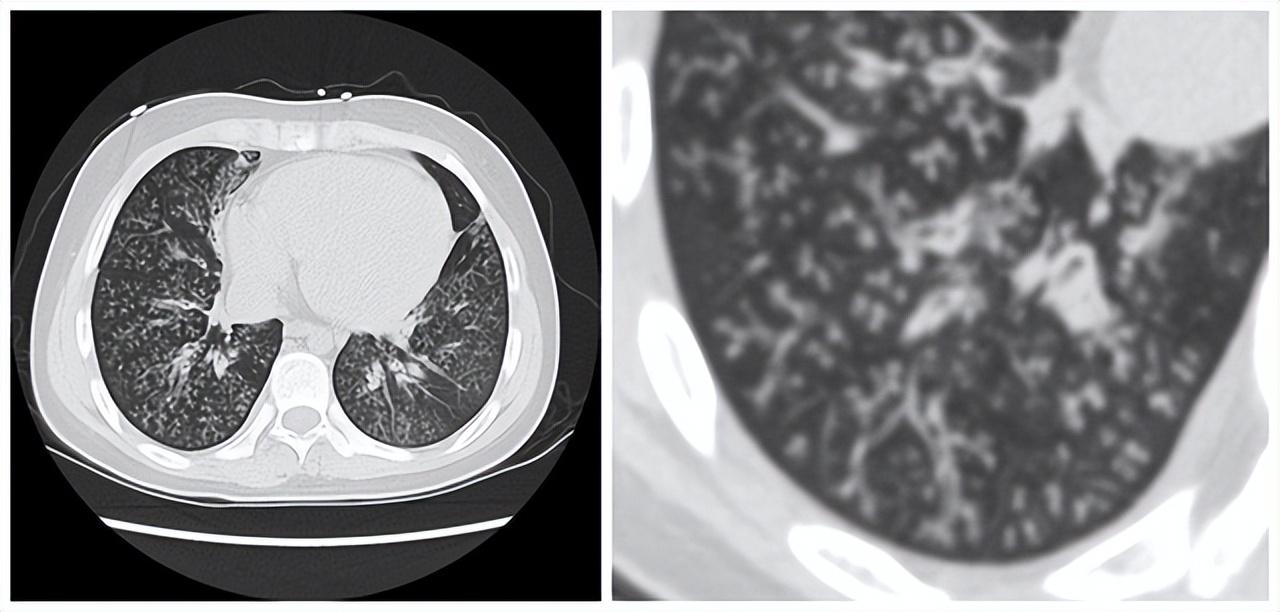

有很多比肺癌还要痛苦的肺病,90%的人都不知道。但患上了以后就很难根治,今天讲的这个疾病就是其中之一。 这个疾病有一个特异之处,就是经常合并有鼻炎,鼻窦炎。刚开始的时候主要的症状是咳嗽咳痰,症状会随着病情的加重而加重,并且出现气喘的情况。肺功能通常会出现阻塞性的通气功能障碍,这个疾病还有另外一个非常特征性的表现,就是胸部CT上的树芽征。 所谓的树芽征,就是肺部的细支气管周围长出类似于树芽的表现,像冬天梅花的花骨朵与树枝的关系,通常这种树芽征会呈现出下肺为主的弥漫性分布,这种表现是造成患者肺功能下降的主要机理之一,它会阻塞压迫细支气管,使呼吸变得不通畅,人逐渐出现气喘。这个疾病最终的发展会导致不可逆的支气管扩张和慢性阻塞性肺病,终末期患者非常难受,痛苦程度不亚于肺癌。 说来奇怪,这个疾病治疗又非常简单,主要靠大环内酯类的药物,比如说红霉素或者阿奇霉素长期口服为主,这两个药属于抗生素,但在这个疾病的诊治过程中,主要起到的作用不是抗感染,而是免疫调节。患者服用药物之后,肺部的树芽征可以逐渐好转,甚至消失。但如果进入了支气管扩张的终末期阶段,病情就很难逆转,所以疾病要早诊早治。所以记住这个疾病的特征是鼻窦炎加上肺部的树芽征及咳嗽咳痰气喘的表现。有这样的表现的病人一定要想到这个疾病。